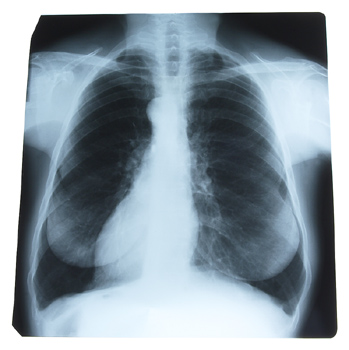

Results of the most comprehensive analysis to date of the impact of gender differences in lung cancer incidence in the United States indicate that lung cancer rates among men are on the decline, while the rate in women remains steady.

A new study in the March issue of CHEST, the peer-reviewed journal of the American College of Chest Physicians, shows that, in addition to the unequal incidence of lung cancer in men and women, there are other gender-linked differences, including subtype of lung cancer and survival rate.